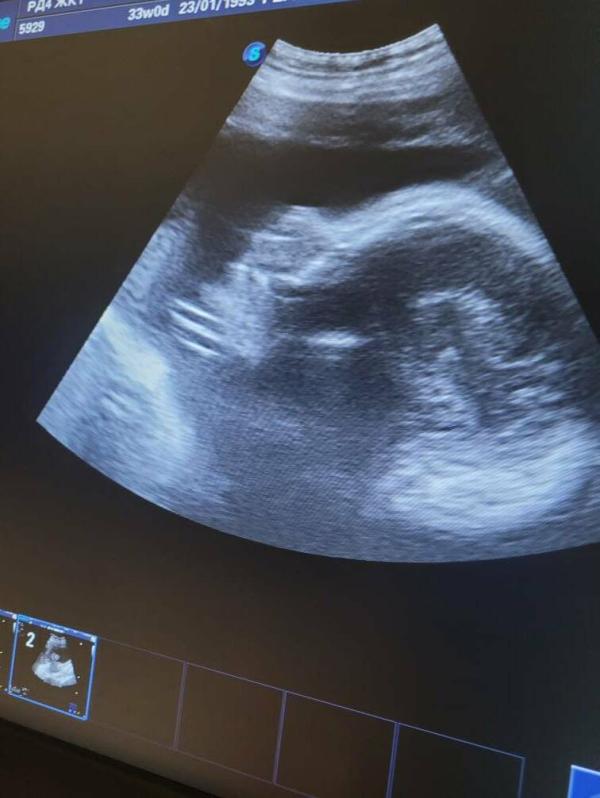

Девочки добрый вечер, была на УЗИ, сегодня все хорошо, только врач сказала двойное обвитие пуповиной вокруг шеи, сказала что такое бывает у 70% детишек, а я теперь на нервах, скажите стоит ли так переживать 🤔😒?